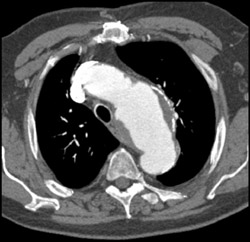

Aortic Aneurysm